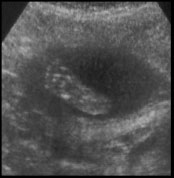

And now for the pictures. I'm only putting up two... they're the best of the lot we got.

Her footprint. Such precious little feet will eventually keep me up at night.